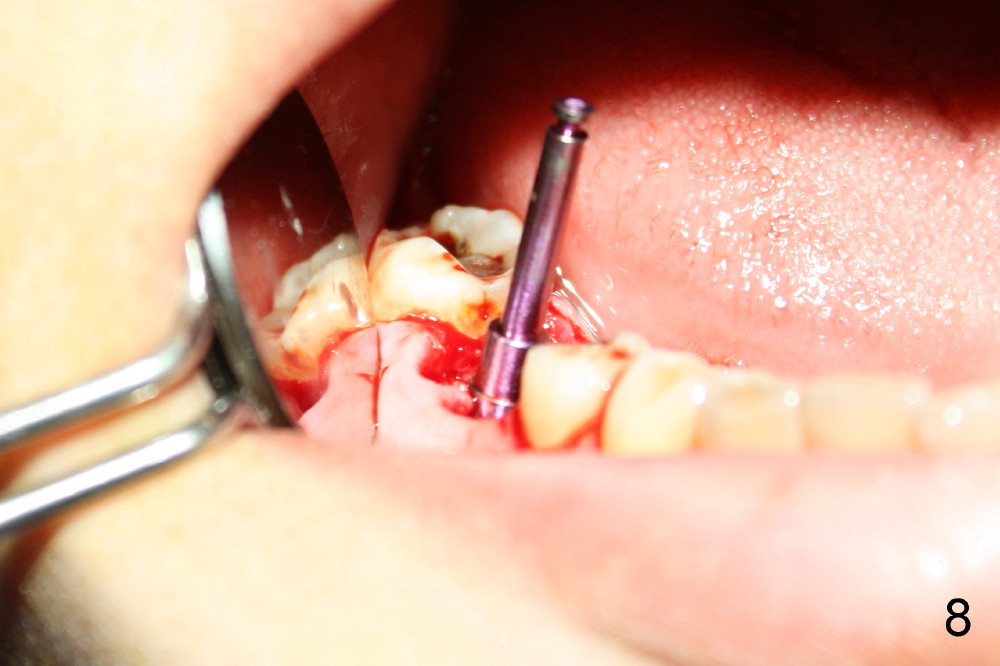

A 38-year-old lady agrees to have implant placement 7 years after loss of the crown of the lower right first molar (Fig.1,2). When the tooth is extracted, the septum is found to be low (Fig.3,4). To confirm it, a PA is taken (Fig.5). To initiate an osteotomy in the septum, it is trans-sectioned with thin osteotomes as shown in Fig.4 insert (black line). A 2 mm pilot drill is placed in the septum (Fig.6: P). The osteotomy is enlarged by 2.5-4.0 mm reamers (Fig.7,8), followed by insertion of 6x17 mm tapered tap at the depth 14 mm (Fig.9). The osteotomy is further enlarged by 4.5 and 5.0 mm reamers. A 6.0x14 mm one piece implant is placed initially. The trajectory is not ideal. A 6.0x14 mm one piece implant is placed initially. The trajectory is not ideal. The implant is removed from the osteotomy partially and reinserted with improved trajectory (Fig.11, compare to Fig.10 (red line)). Primary stability is high. There is not much bone mesiodistally so that the trajectory is easily changed in that direction. After abutment preparation, mixture of autogenous bone (harvested from reamers) and allograft is placed in the residual mesial and distal sockets (Fig.12). To contain the bone graft, an immediate provisional is placed (Fig.13 P). The occlusal plane of the provisional is significantly lower than that of the adjacent teeth to avoid micromovement of the implant. The patient is advised to eat soft food on the left side. Six days postop, the patient returns for prophy. The provisional is removed; the bone graft appears to be incorporating into the socket (Fig.14). After recementation, the provisional remains in place for 3.5 months; PA shows increased bone density in the mesial and distal sockets (Fig.15, compare to Fig.5,11). Due to insurance coverage, the patient defers fabrication of definitive restoration for at least 7 months. The immediate provisional is finally lost 8.5 months postop: the gingiva attaches to the 1-piece implant (Fig.16), while the density of the mesial socket increases (Fig.17 *) with formation of the cortex (lamina dura) coronally (v). Before the provisional (Fig.18 P) is removed for cementation of the definitive restoration, black shadow (*) is noted over the buccal gingiva. It is partially due to buccal placement (Fig.19) and partially due to buccal atrophy over a period of 10.5 months postop. How to prevent buccal placement? Positioning the first pilot drill in the septum buccolingually is a key. Eleven months post crown (Fig.20 C) cementation, the black shadow remains, but there is no tenderness. If the implant threads are immediately underneath the periosteum, there is tenderness.